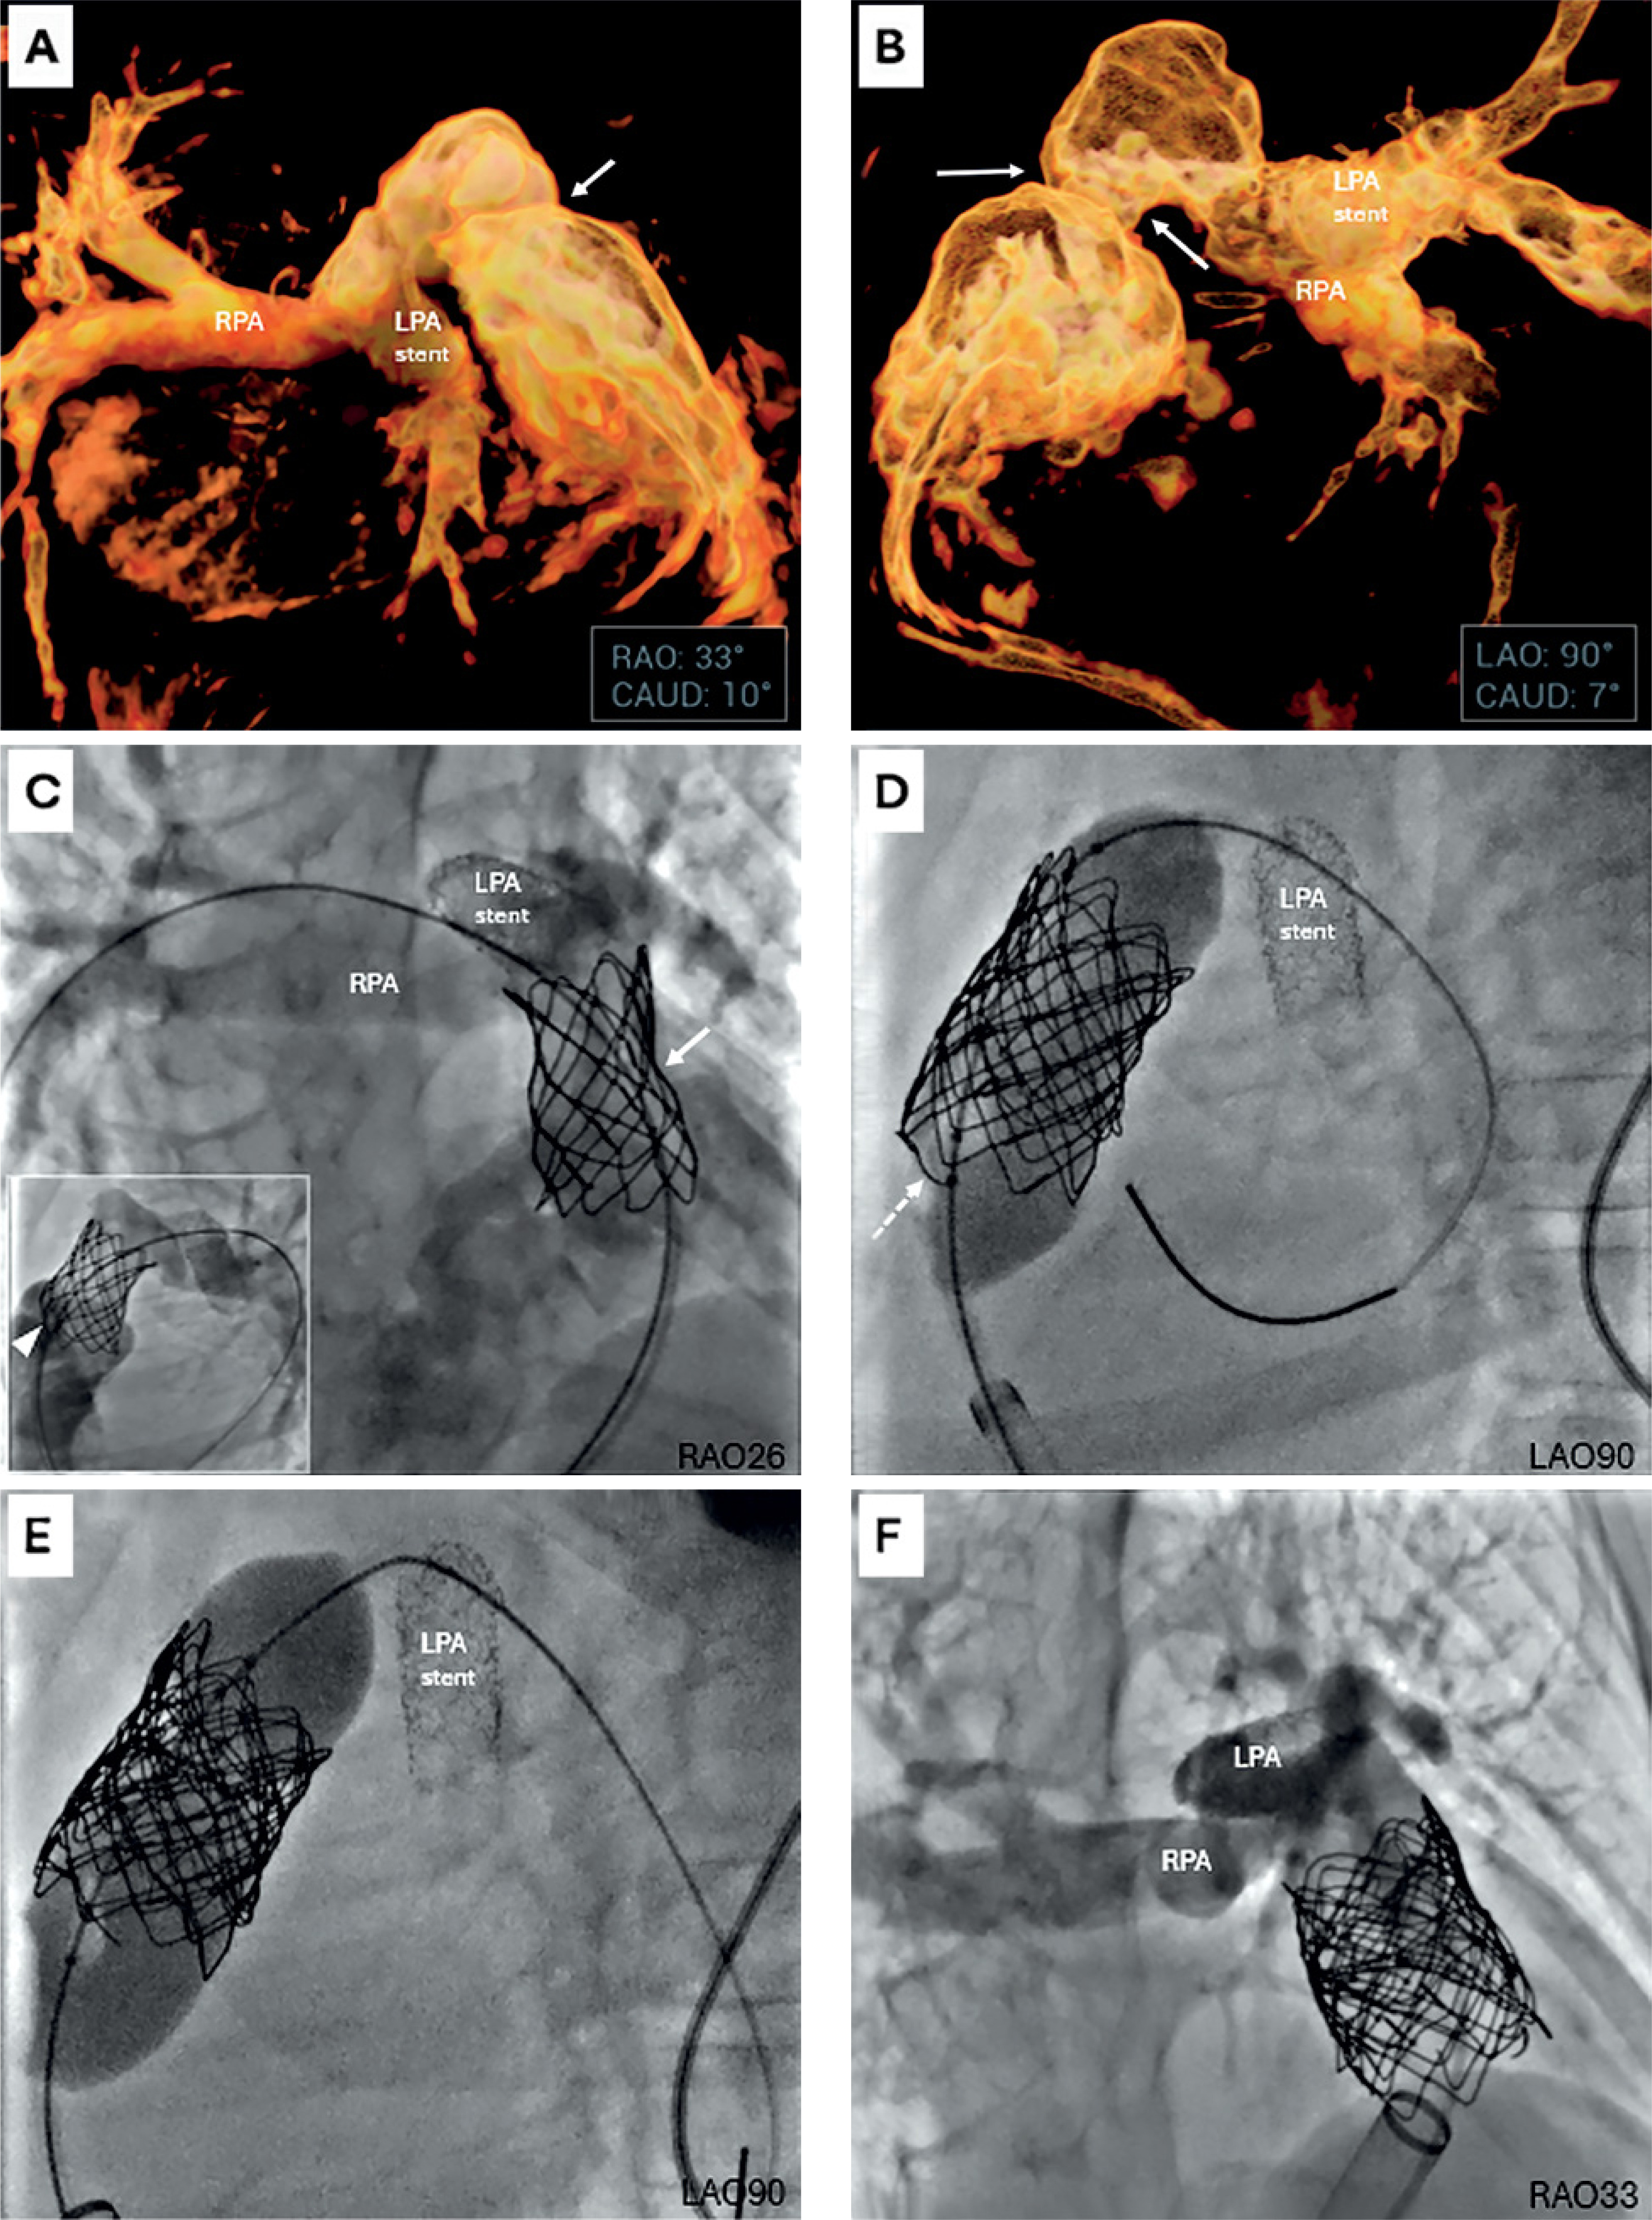

After syncope and frequent premature ventricular contractions during rehabilitation, urgent TPVI was indicated. Due to contrast allergy and neurological comorbidities, pre-procedural computed tomography (CT) was omitted. Planning relied on virtual reality modelling based on three-dimensional rotational angiography from the previous catheterisation (Figures 1 A, B).

Figure 1

Virtual reality-guided planning and stepwise Melody valve implantation bypassing the Ensemble delivery system. A, B – Virtual reality (VR) reconstructions generated from three-dimensional rotational angiography (3DRA) performed at a prior catheterization. A – Right anterior oblique projection with mild caudal angulation (RAO 33°/CAUD 10°) demonstrating the spatial orientation of the pulmonary arteries (RPA – right pulmonary artery; LPA stent – previously implanted stent in the left pulmonary artery) and proximal narrowing of the right ventricle-to-pulmonary artery (RV-PA) graft (white arrow). VR was used to identify optimal working angles for subsequent catheterization, later confirmed during angiography (C, F). B – Left anterior oblique projection with mild caudal angulation (LAO 90°/CAUD 7°) highlighting the tight proximal narrowing at the RV-PA graft anastomosis (white arrows), which subsequently became the site of proximal infolding of the previously implanted CP stent (NuMed). C–F – Stepwise course of Melody (Medtronic) valve implantation directly on a balloon-in-balloon (BIB, NuMed) catheter, bypassing the Ensemble (Medtronic) delivery system. C – Initial angiography (main panel: RAO 26) demonstrating mild stent narrowing (white arrow) within the right ventricular outflow tract (RVOT). The LPA contains previously implanted stents of appropriate diameter, with mild protrusion into the RVOT but without flow obstruction. A guidewire is advanced deeply into the RPA. Inset (LAO 90) shows proximal RVOT stent infolding (white arrowhead). D – Disruption of the previously implanted RVOT stent (white dashed arrow), reinforced with a 39 mm CP stent on a 22 × 45 mm BIB balloon, creating a secure landing zone for Melody valve deployment. E – Melody valve mounted directly on a 20 × 45 mm BIB catheter positioned in the newly prepared RVOT. A sufficient distance is maintained from the LPA stent, avoiding interference and eliminating the need for deep advancement of the long, bulky proximal shaft (“carrot”) into the pulmonary artery branch. F – Final angiography in the RAO projection (corresponding to panel A) confirming optimal valve expansion, competent function, and unobstructed flow to both pulmonary arteries

Initial angiography showed proximal RVOT stent infolding and mild LPA stent protrusion into the RVOT (Figure 1 C). Due to contrast allergy and comorbidities, the LPA-stent angioplasty was deferred to minimize contrast exposure and procedure time. RVOT pre-dilatation with a 22 × 20 mm Atlas (Bard) balloon caused tearing of the RVOT stent, which was reinforced with an additional 39 mm CP stent deployed on a 22 × 45 mm BIB catheter (Figure 1 D). Despite correct guidewire position and previous successful stent delivery, the Melody valve could not be advanced on the Ensemble system due to mechanical obstruction from the protruding LPA stent.

The operator removed the entire system, manually crimped the valve onto a 20 × 45 mm BIB balloon, and successfully deployed it over the existing guidewire in the stented RVOT (Figure 1 E), followed by post-dilation with a 22 × 40 mm Atlas balloon. Final angiography confirmed an optimal result (Figure 1 F). The patient was discharged on day 3 on aspirin. Three-month follow-up confirmed competent valve function, no new arrhythmias, and satisfactory exercise tolerance.